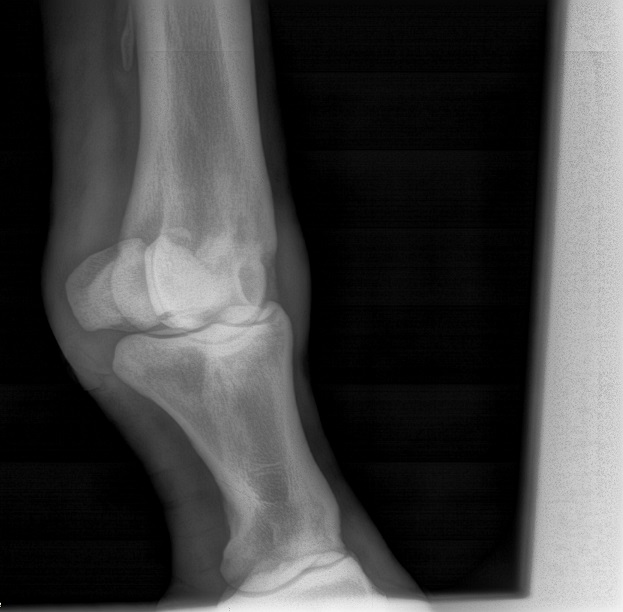

Just wanting to see if anyone had any opinions on these X-rays. Diagnosis was a fractured sesamoid bone. Before and after X-rays in the pics. Do they look any better? Does he have any hope for a barrel future? Anyone experienced this before? Completely sound in the pasture at this time. Has not been put back to work yet. Thanks man advance.

(6-1-16 side2.jpg)

Still looks like a chip is floating around in there.

How old is this horse? I do see what looks like a bone chip floating around

The vet has said it has calcified some. He hasn't said anything about a chip in there. I don't know if it is something that will break off or just calcify and heal up in the next few years.